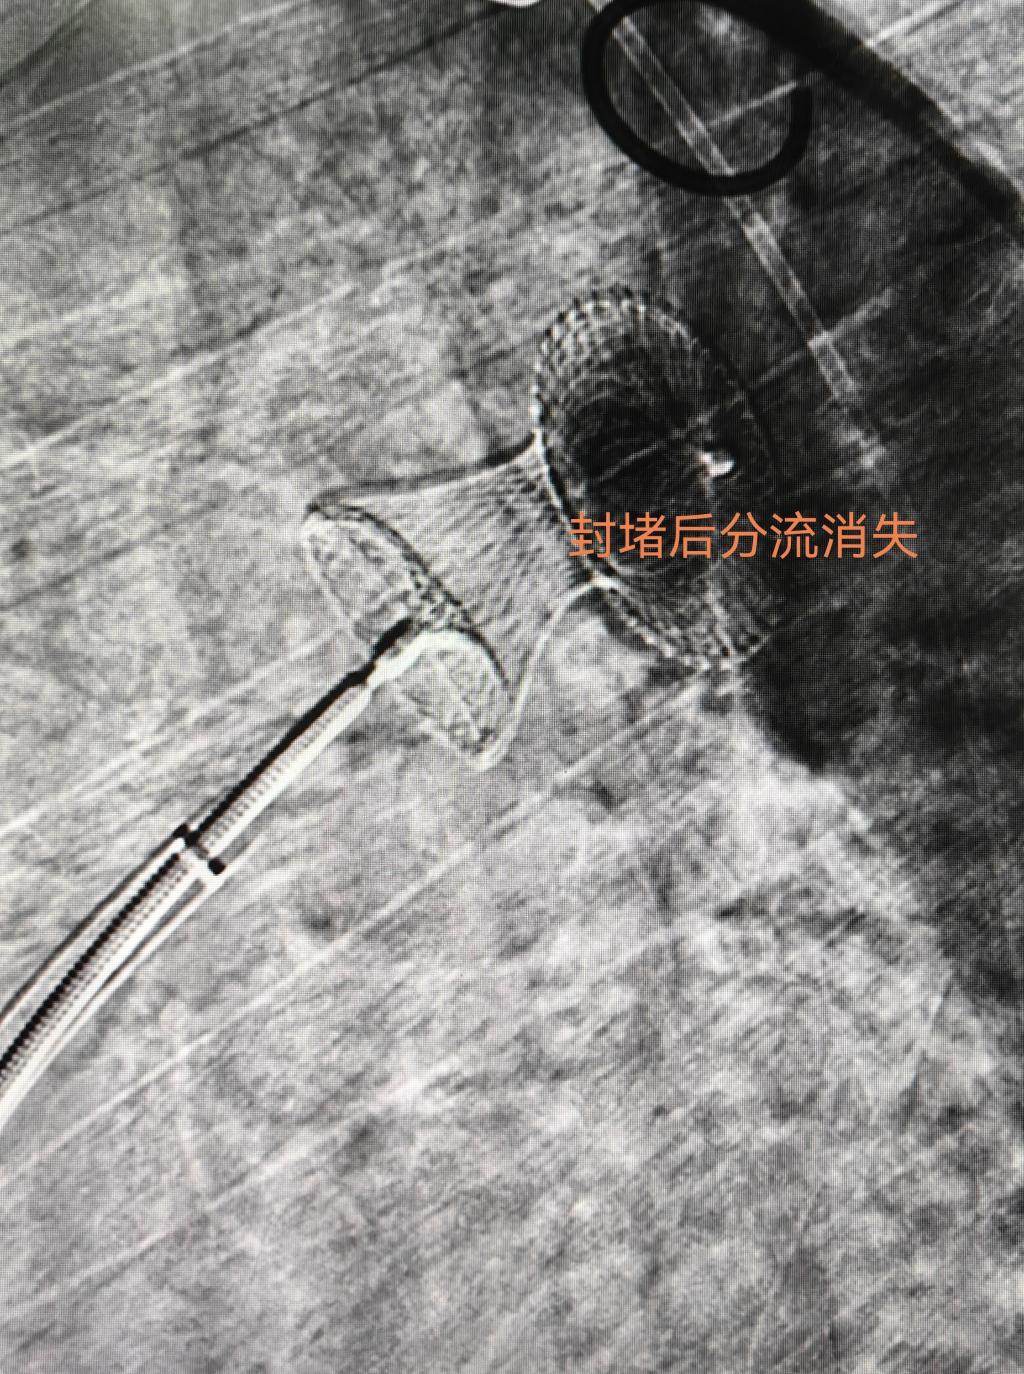

入院后第五天,完成充分的术前准备后,由相里伟医生主刀,张忆雯医生和董泽平医生协助,在导管室人员的配合下,按计划进行介入手术。血管穿刺,主动脉造影,肺动脉测压都顺利完成,也完全证实了术前影像学测量及病情判断。术中遇到的“拦路虎”是经肺动脉通过PDA困难,就改从主动脉侧超选择进入肺动脉,经股动脉送入圈套器去抓捕股静脉侧预置在腔静脉或肺动脉的导丝,期间经历了圈套器无法进入腔静脉和右心室敏感极易诱发阵发性室速等障碍,经过手术团队耐心的尝试,默契的配合和精巧的技术操作下成功建立了封堵器释放轨道。最关键的时刻到了,当封堵器沿着输送鞘缓慢送达降主动脉位置,依次释放主动脉侧封堵盘,封堵器腰部,肺动脉侧封堵盘,透视下腰征清晰,牵拉实验稳定,造影分流完全消失,听诊心前区杂音完全消失,动脉导管未闭介入封堵获得成功,意味着患者可以避免创伤大风险高的外科手术(图3、4、5)。更令人欣喜的是,当动脉导管未闭治愈的同时,左右心房间的卵圆孔未闭分流也瞬间消失了,甚至导丝尝试通过也变得很困难,再去处理卵圆孔未闭也已经失去必要性了,单纯动脉导管未闭封堵手术达到了“一石二鸟”良好疗效。